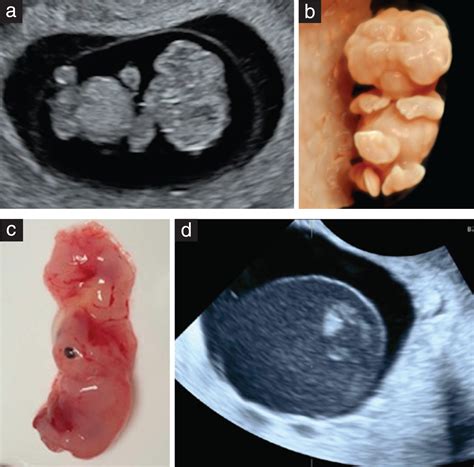

• Miscarriage: The scan can detect signs of a miscarriage, such as a lack of fetal heartbeat or an empty gestational sac.

• Ectopic Pregnancy: An ectopic pregnancy occurs when the fertilized egg implants outside the uterus, typically in the fallopian tube. The scan can help identify this condition.

• Molar Pregnancy: A molar pregnancy is a rare condition where abnormal tissue develops instead of a fetus. The scan can detect the characteristic appearance of a molar pregnancy.